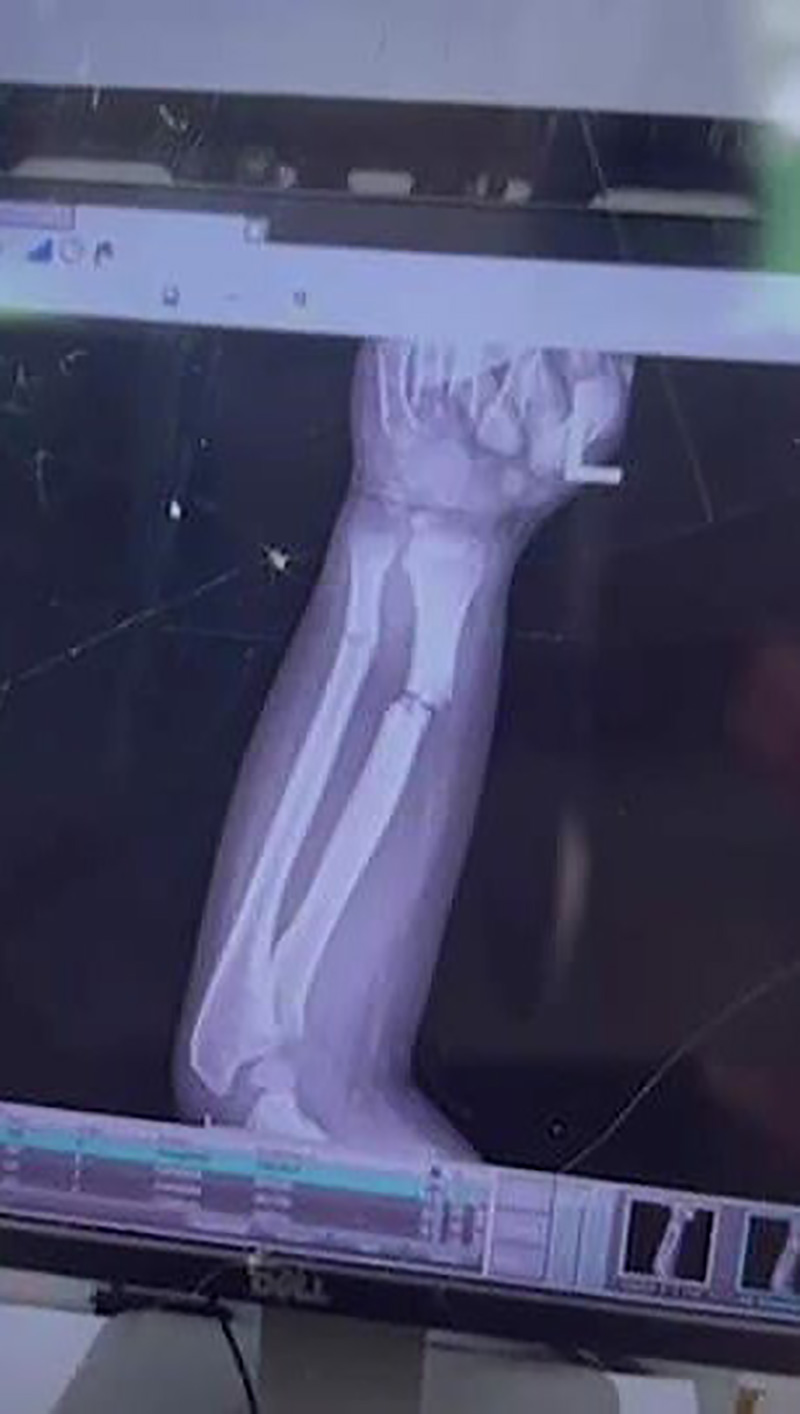

โดยนางสาวกรรณิการ์ เล่าว่า ตนเลี้ยงน้องเตเต้มาตั้งแต่อายุ 3 ขวบ เพราะพ่อแม่น้องไปทำงานอยู่ต่างจังหวัด ปกติแล้วคนในครอบครัวจะผลัดกันไปรับ-ส่งน้องเตเต้ที่โรงเรียน เพราะบ้านอยู่ไม่ห่างจากโรงเรียนมากในวันเกิดเหตุ วันที่ 13 มิถุนายน ตนขอให้พี่ชายไปรับน้องเตเต้ให้หน่อย เพราะติดงาน จนประมาณ 16.00 น. พี่ชายวิ่งมาบอกว่าหลานแขนหัก จึงรีบกลับบ้านมาดูอาการหลาน พบว่าน้องเตเต้ร้องไห้ตัวสั่น แขนซ้ายหักผิดรูป พอสอบถามน้องบอกว่า แขนหักตั้งแต่ตอนเที่ยง ครอบครัวจึงรีบพาน้องเตเต้ส่งโรงพยาบาลนางรอง เพราะโรงพยาบาลหนองกี่ที่อยู่ในพื้นที่ไม่มีหมอด้านกระดูก ซึ่งกว่าจะถึงมือหมอก็ 4 ทุ่มแล้ว